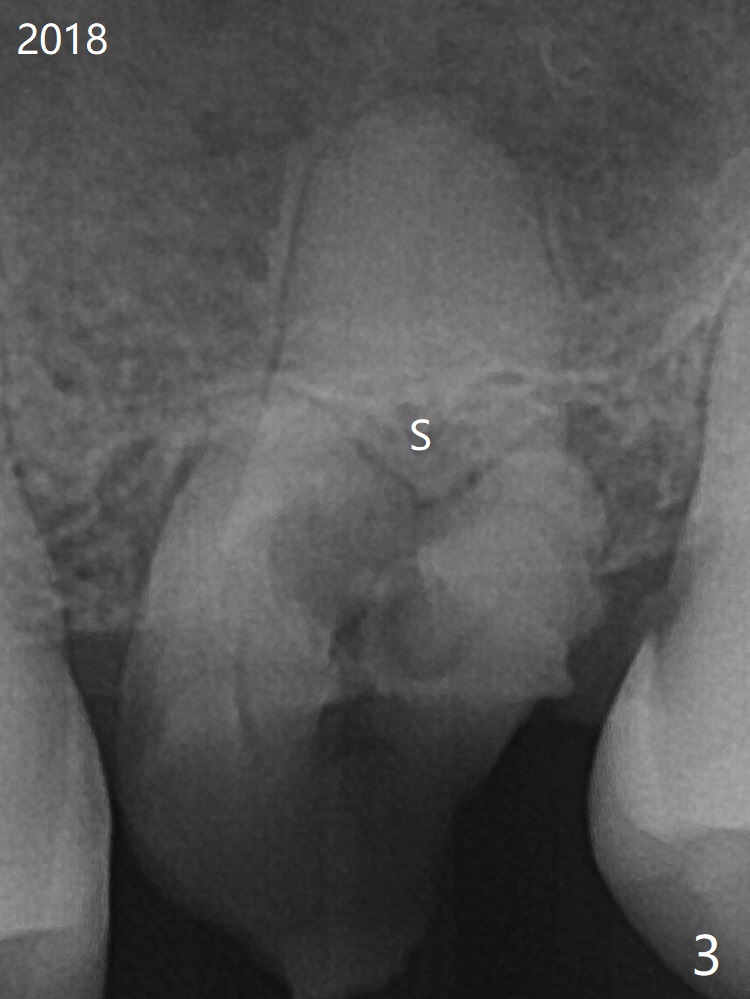

A 59-year-old nervous woman has poor dentition with upper left pain (Fig.1). Composite was placed at #12 and sedative filling at #13 two years ago. If the tooth #14 causes discomfort, it should be extracted for bone graft or immediate implant (Fig.4). PRF will be prepared (x2, white and red). The implant will be placed slightly palatal (P, Fig.2), since the residual buccal roots are more likely associated with buccal plate bone loss. If she agrees with treatment planning, take 5x5 cm CT for the bone loss and sinus. Sinus lift seems necessary because of short bone and septum (Fig.2,3).